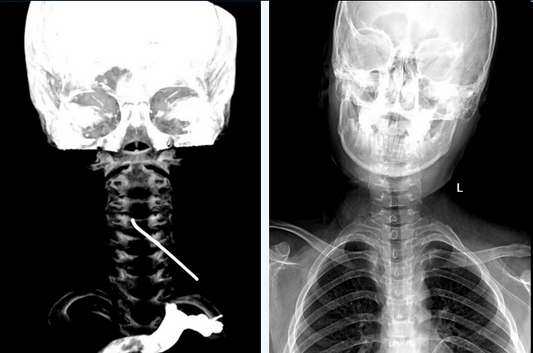

Managing Medically Refractory Acute Stroke: Cli...

This case highlights a 68-year-old female patient whose neurological status rapidly deteriorated to complete hemiplegia despite medical therapy. The Expert Team at Beijing Fuwai Hospital successfully restored TICI Grade 3...